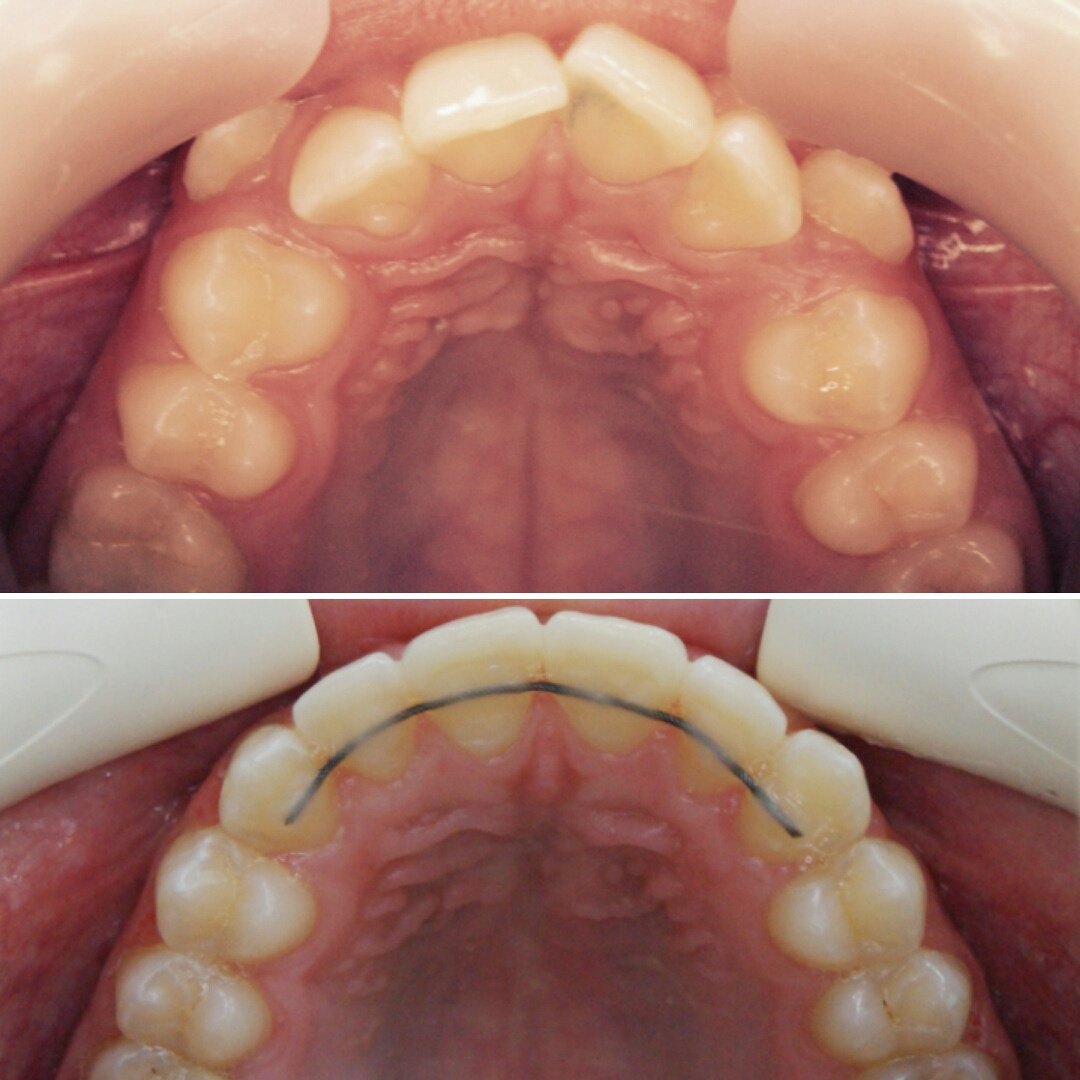

Эта фраза знакома многим ответственным родителям, которые привели на приём к ОРТОДОНТУ своего ребёнка в 5-10 лет, заподозрив проблему или понимая, что места постоянным зубам откровенно не хватает! Горькая правда в том, что брекеты - не волшебное средство от всех проблем, они "расставляют" зубы внутри сформированого объёма челюсти, но никак не влияют на её рост. Родители ждут, а тем временем драгоценное время, когда ребёнок растёт, уходит... Во взрослом возрасте приходится удалять здоровые зубы или прибегать к ортогнатической хирургической операции. 📸 На фото узкая нижняя челюсть, места постоянным зубам нет, боковые резцы прорезываются "вторым рядом".

✅ Помогаем с помощью расширяющей дуги, пружины и зацепных элементов, которые зафиксированы на МОЛОЧНЫЕ зубы

ЧАСТЬ 1. АППАРАТАТ МАРКО РОСА (Marco Rosa) или аппарат для быстрого нёбного расширения. Это ортодонтический аппарат, названный так в честь своего создателя - итальянского доктора ортодонтии Marco Rosa.

▶️ Аппарат устанавливается на верхнюю челюсть, у него есть пластмассовый базис, в который встроен винт. При раскручивании винта, половинки аппарата раздвигаются , передавая силу давления винта на зубы и твёрдое нёбо, верхняя челюсть расширяется.

КОНСТРУКЦИЯ АППАРАТА МАРКО РОСА

1️⃣ ВИНТ ХАЙРЕКС. Создаёт расширяющее усилие.

2️⃣ МЕТАЛЛИЧЕСКИЕ ЛАПКИ. Это дополнительные элементы фиксации, которые упираются в молочные клыки, создают точки приложения силы к зубному ряду.

3️⃣ КОЛЬЦА НА МОЛОЧНЫЕ МОЛЯРЫ. Обеспечивают фиксацию аппарата на опорных зубах с помощью специального стоматологического клея.

4️⃣ ПЛАСТМАССОВЫЙ БАЗИС (пластинка). Объединяет все элементы в единую систему и передаёт расширяющее усилие винта на нёбо.

5️⃣ ДОПОЛНИТЕЛЬНЫЕ ЭЛЕМЕНТЫ (крючки для лицевой маски)